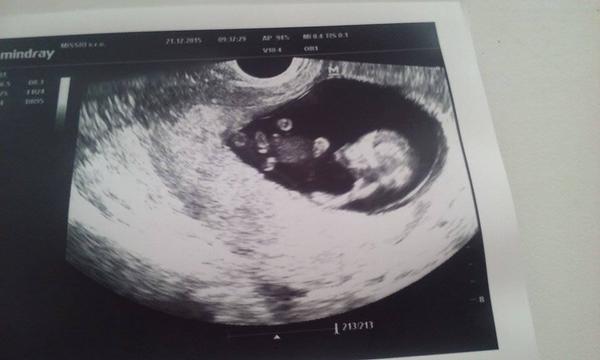

@chevalbleu jej to su krasne fotecky.. dufam tu bude takych buduci rok len a len pribudat..

@mozartka Boze moj, to je zlate! Akoby lezalo na boku a podopieralo si hlavu :D Mne sa zase vcera zdalo, ze jedno sa sparalo v nose hehe

@mozartka babyyy vy máte aké krásne fotky 🙂 ten môj sa nonstop vrti :D takze mam len dve take krajšie 🙂 ale vaše sú naozaj nádherné 🙂))

@chevalbleu no prave pozdravoval rukami, lebo tam bol aj ocino a miminko je uz teraz slusny 🙂 Najprv spinkal ale pocas meranie uz normalne skakal, zato je taky zaber 🙂